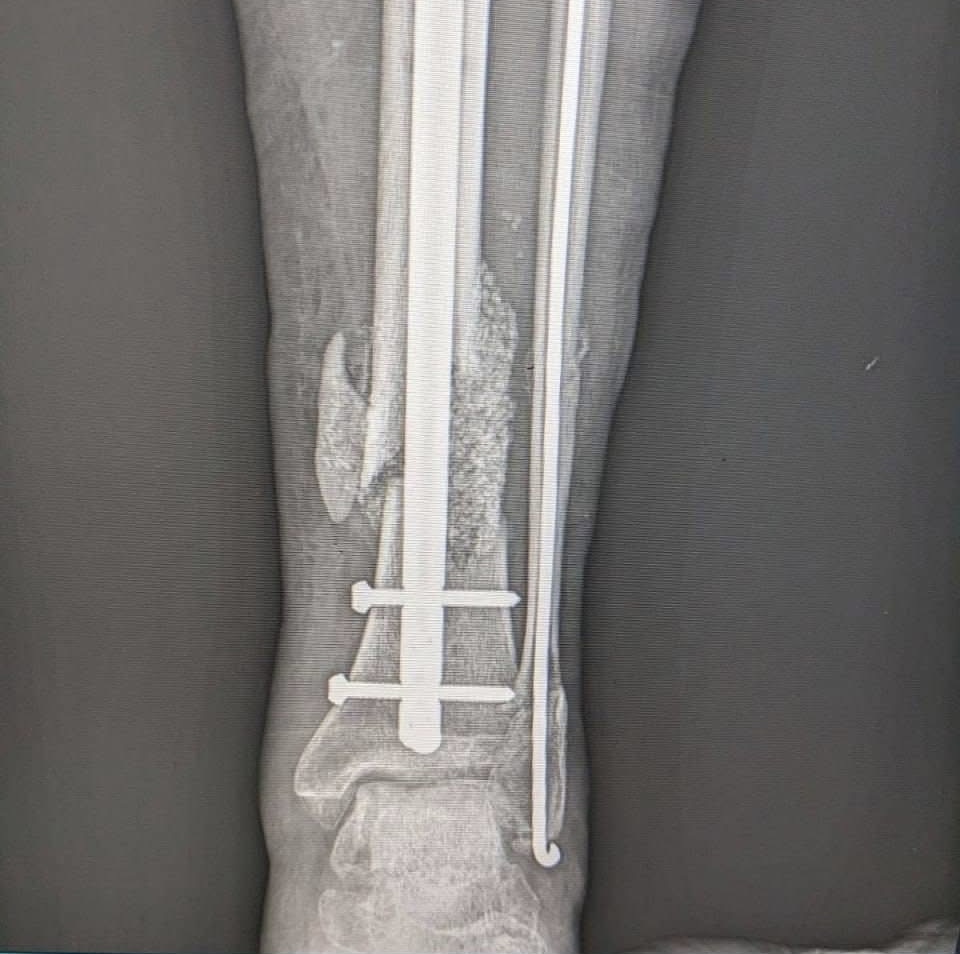

Прикарпатські медики провели складну реконструктивну операцію військовослужбовцю, відновивши пошкоджену кісткову тканину із застосуванням сучасних технологій. Втручання виконала команда травматологів-ортопедів у Богородчанській центральній лікарні.

Пацієнт мав післятравматичний дефект кістки, тож лікарі провели реконструкцію із використанням аутокісткової пластики — власної кісткової тканини пацієнта — у поєднанні з біоактивним склом. Така методика сприяє регенерації тканини, покращує інтеграцію імплантованого матеріалу та знижує ризик ускладнень, що допомагає швидше відновити функції кінцівки.